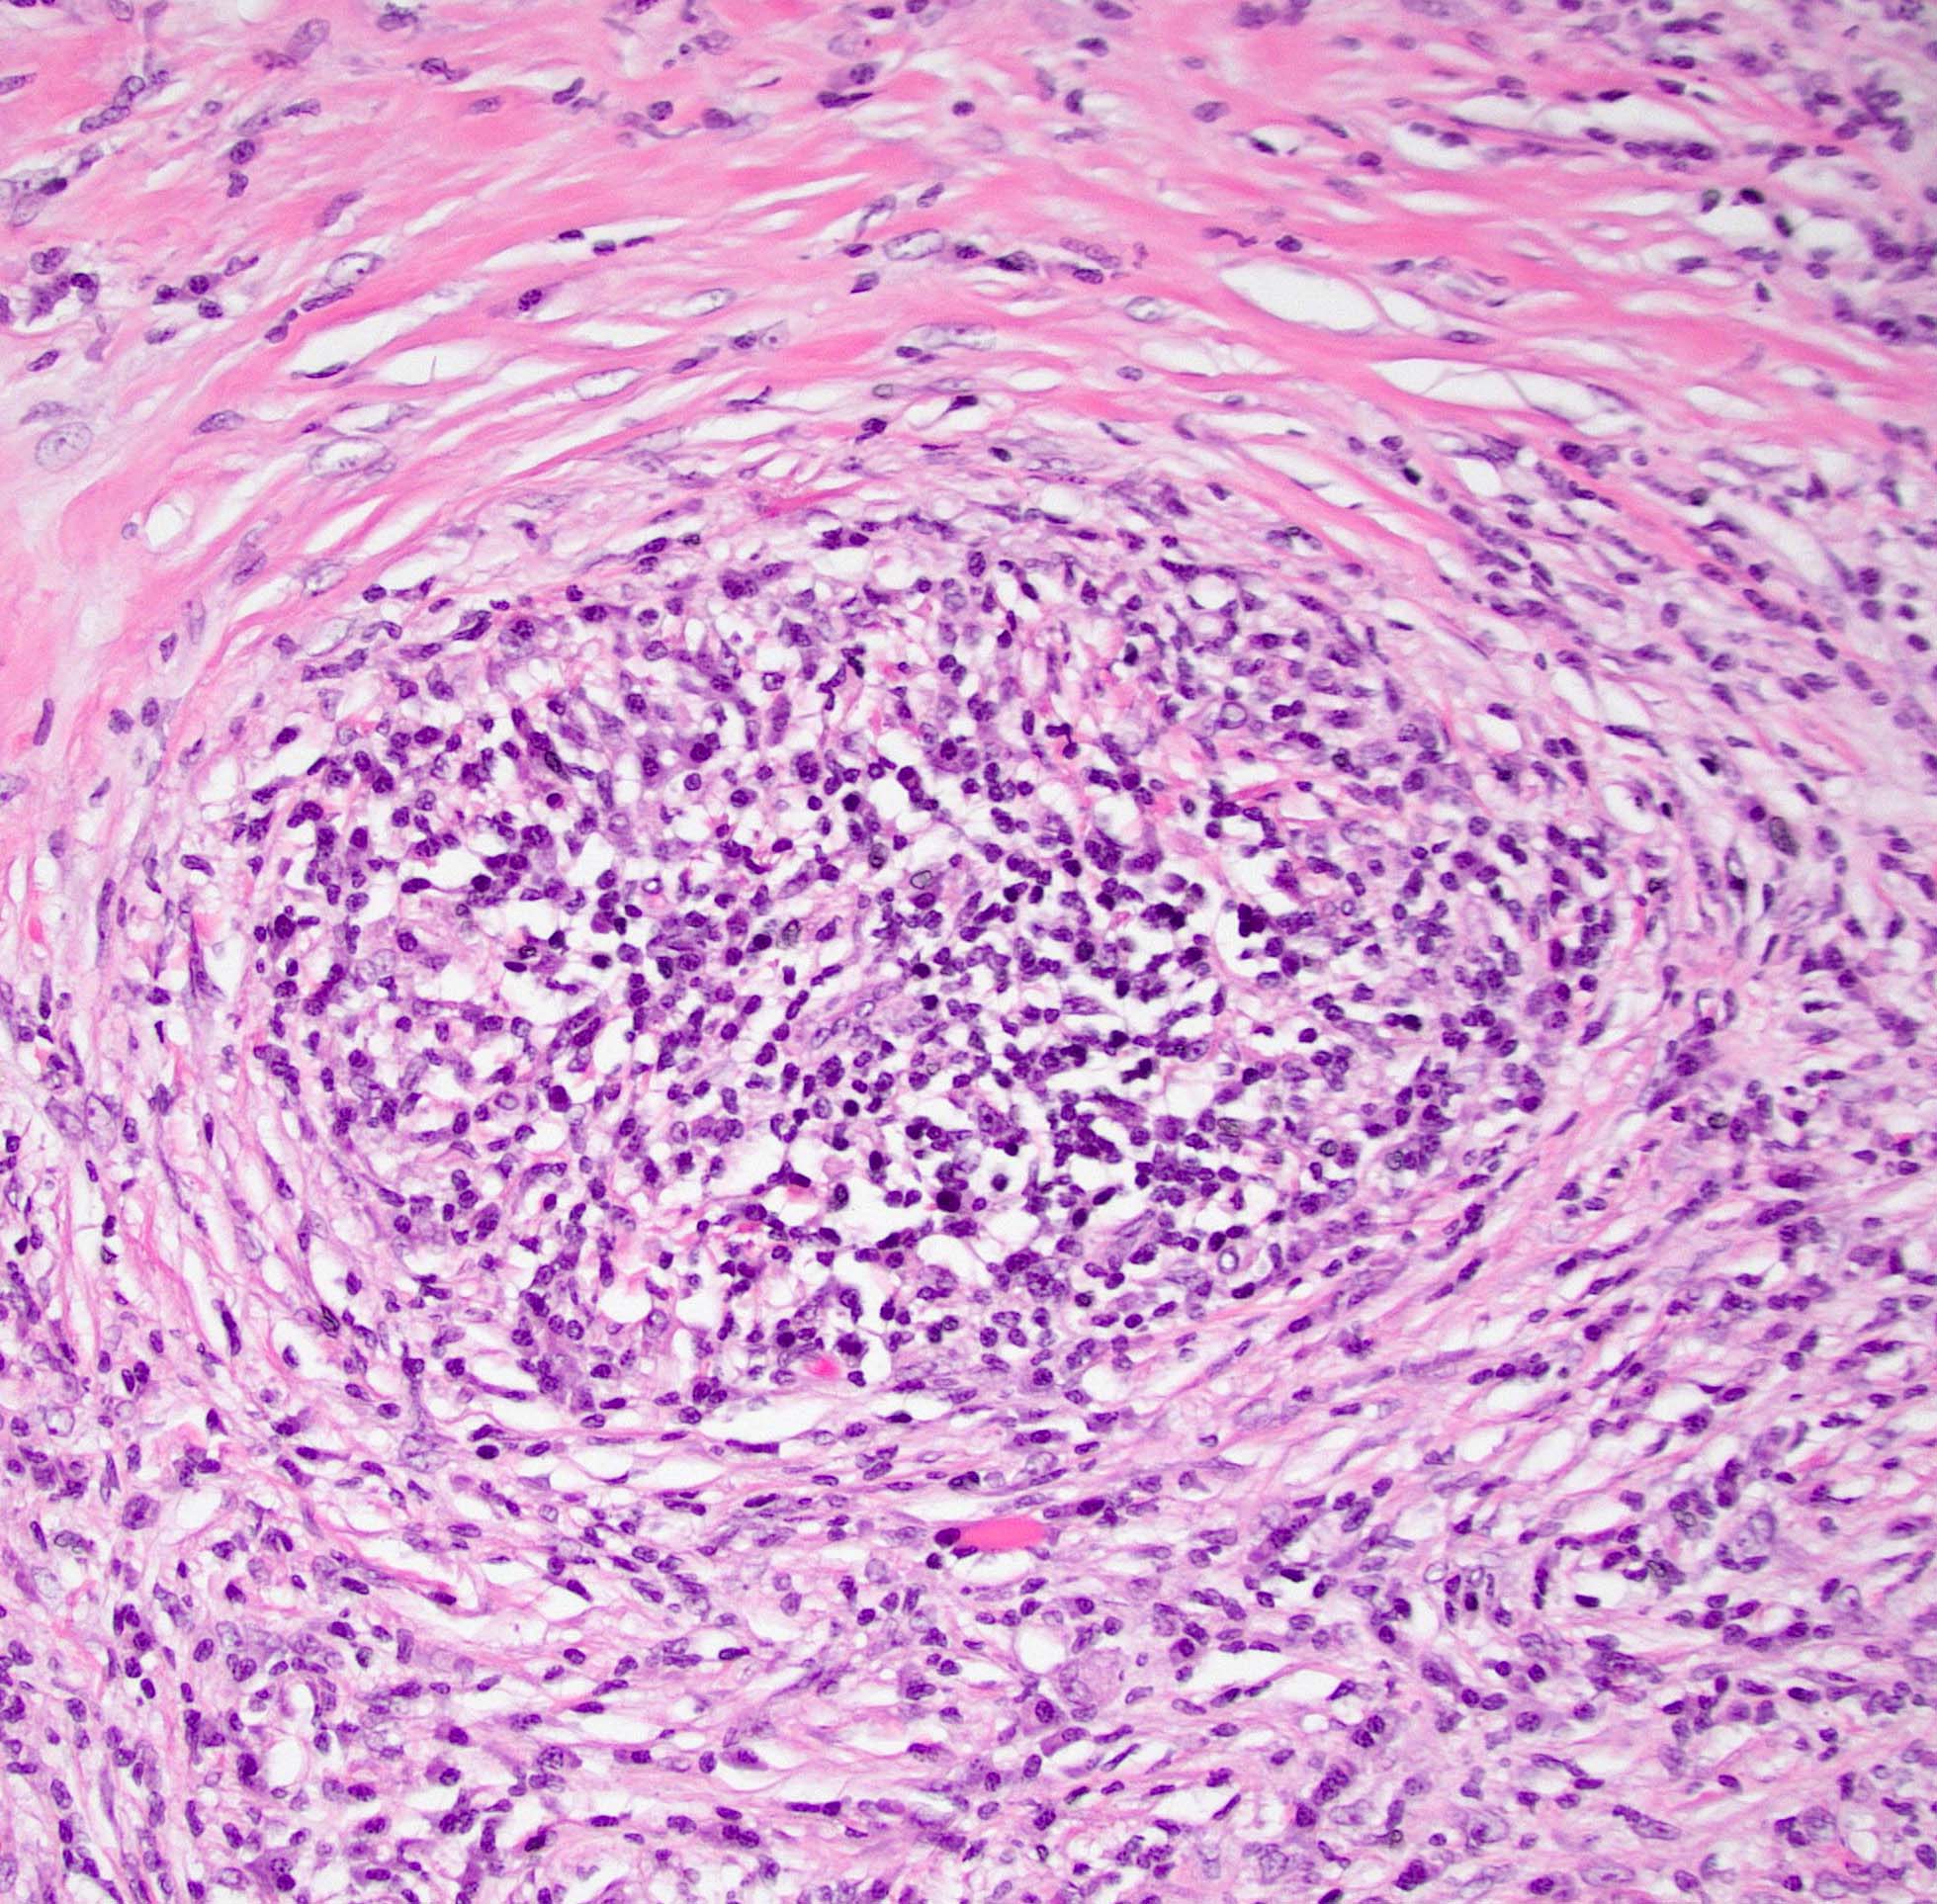

Microscopic (histologic) description

- Characteristic findings (at least 3 for level 1 criteria) (Pancreas 2011;40:352)

- Periductal lymphoplasmacytic infiltrate without granulocytic infiltration

- Obliterative phlebitis

- Storiform fibrosis

- Abundant (> 10 cells/high power field) IgG4 positive plasma cells

- Biopsy showing some but not all of the above features can be used as supportive evidence for the diagnosis of autoimmune pancreatitis (Pancreas 2011;40:352)

- Inflammation is localized within the pancreatic parenchyma and is centered around / within medium to large interlobular ducts, which causes shrinkage of the ductal lumen (Pathologica 2020;112:197)

- Inflammation can also be seen between the pancreatic parenchyma and peripancreatic adipose tissue (Pathologica 2020;112:197)

- Inflammation of the venous wall can progress to obliterative phlebitis with fibrosis of the lumen (Pathologica 2020;112:197)

- As the inflammation progresses, fibrosis becomes more diffuse, assuming a whorled or storiform pattern (Pathologica 2020;112:197)

- Perineural inflammation can also be present (Pathologica 2020;112:197)

- Involvement of the pancreatic neck margin or biliary resection margin should be clearly stated in the pathology report for therapeutic purposes (Pathologica 2020;112:197)

Microscopic (histologic) images